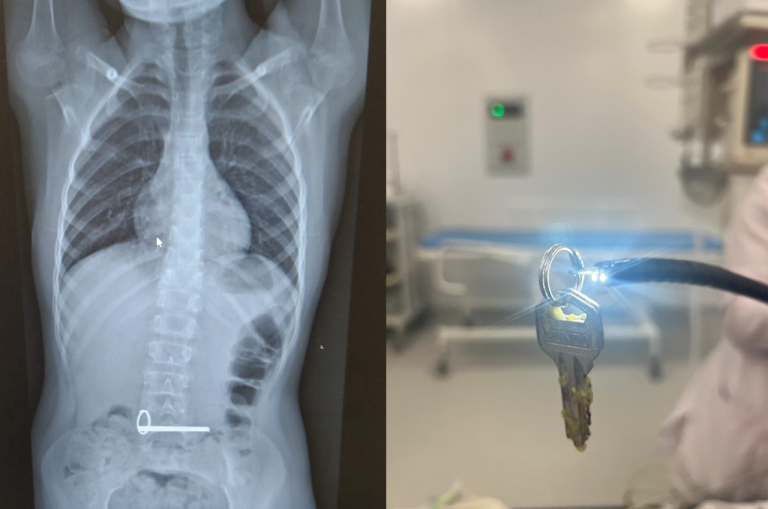

В Оренбуржье восьмилетний ребёнок проглотил связку ключей

Восьмилетний ребёнок поступил в отделение экстренной помощи ОДКБ ночью, с инородным телом в желудке. На снимке были чётко видны два ключа.

Эндоскописты извлекли ключи без каких-либо осложнений для ребёнка, манипуляцию провели под наркозом.

Как отметил заведующий эндоскопическим отделением ОДКБ Андрей Бобров, такие случаи происходят довольно часто. Есть даже своеобразная коллекция предметов: батарейки, орбизы, иголки, гвозди, булавки, заколки, скрепки, одёжные кнопки, магниты и многое другое, что достали врачи отделения из лёгких и желудков у маленьких пациентов.